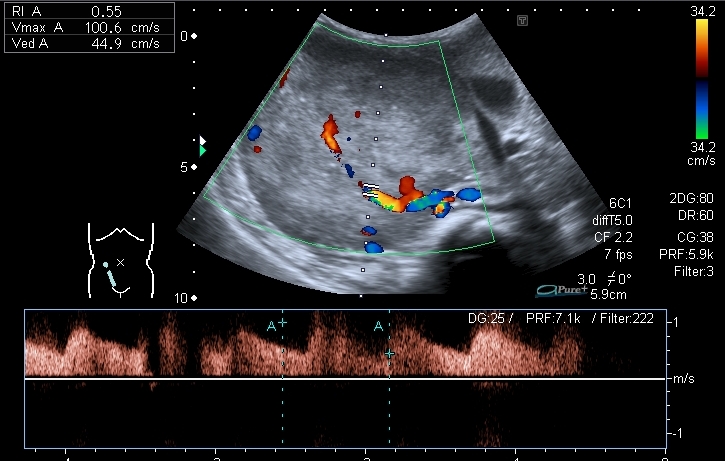

При ЦДК - образование васкуляризировано, кровоток в образовании малорестриктивный.